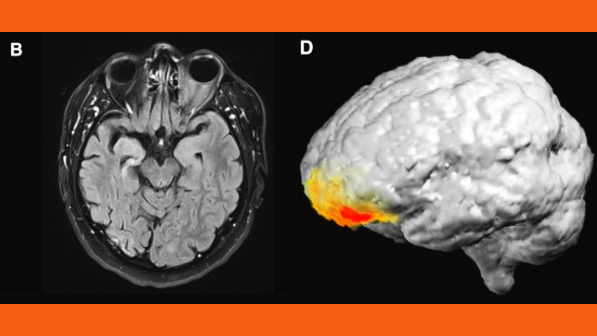

Doctors ran a typical a brain scan on an epilepsy patient. As they were watching, the patient saw God. Here’s what happened next.